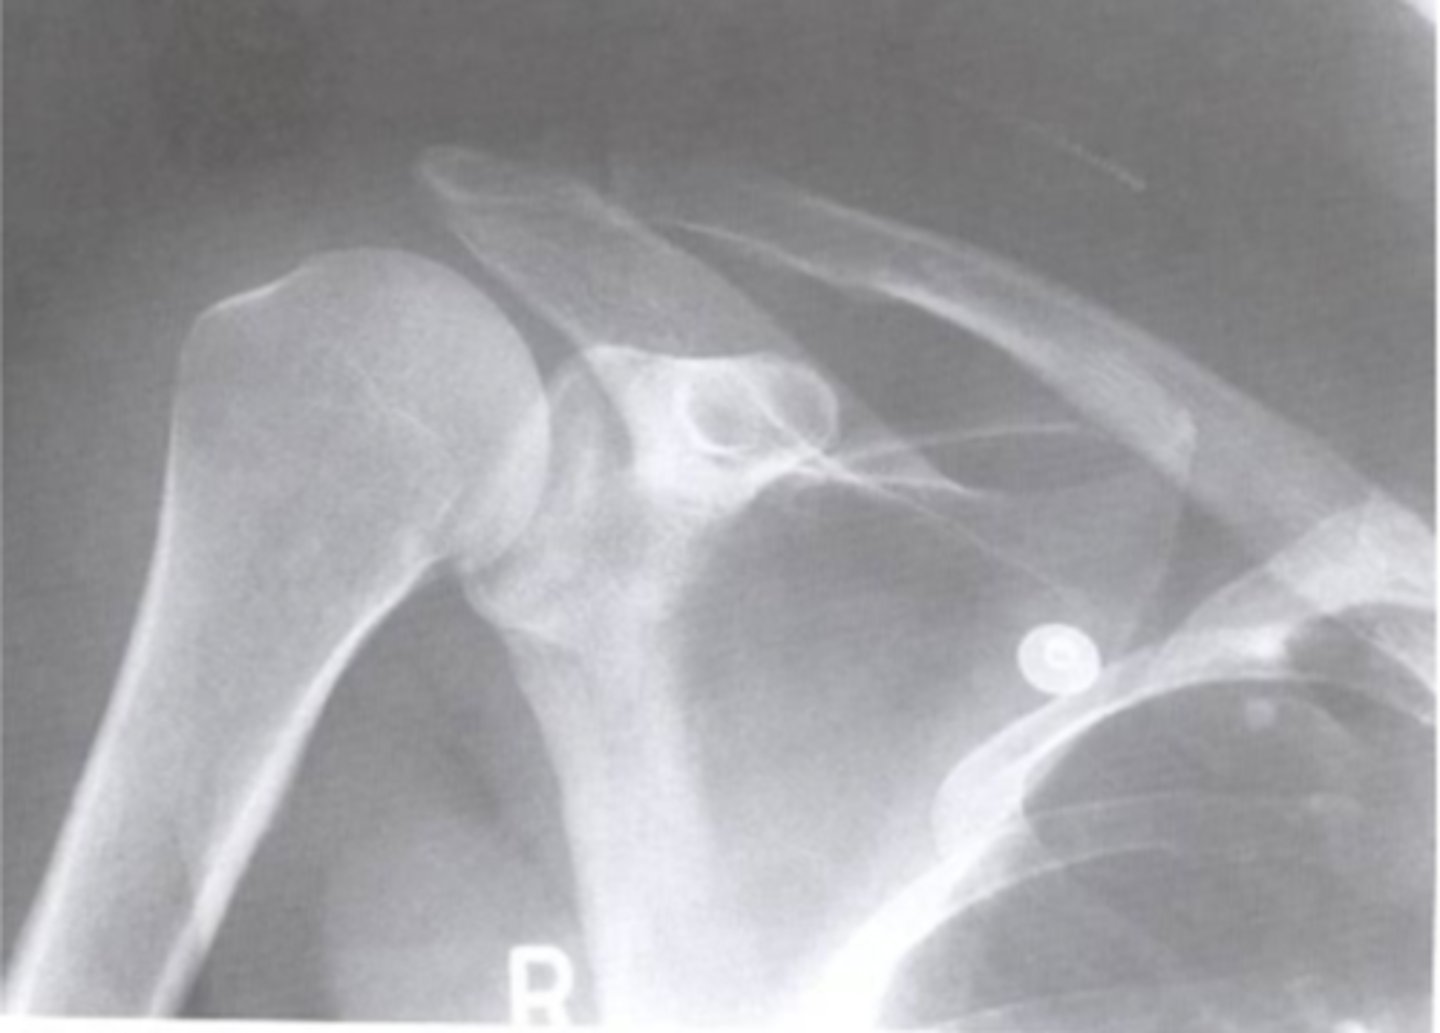

AP of the right shoulder

What view does this show?